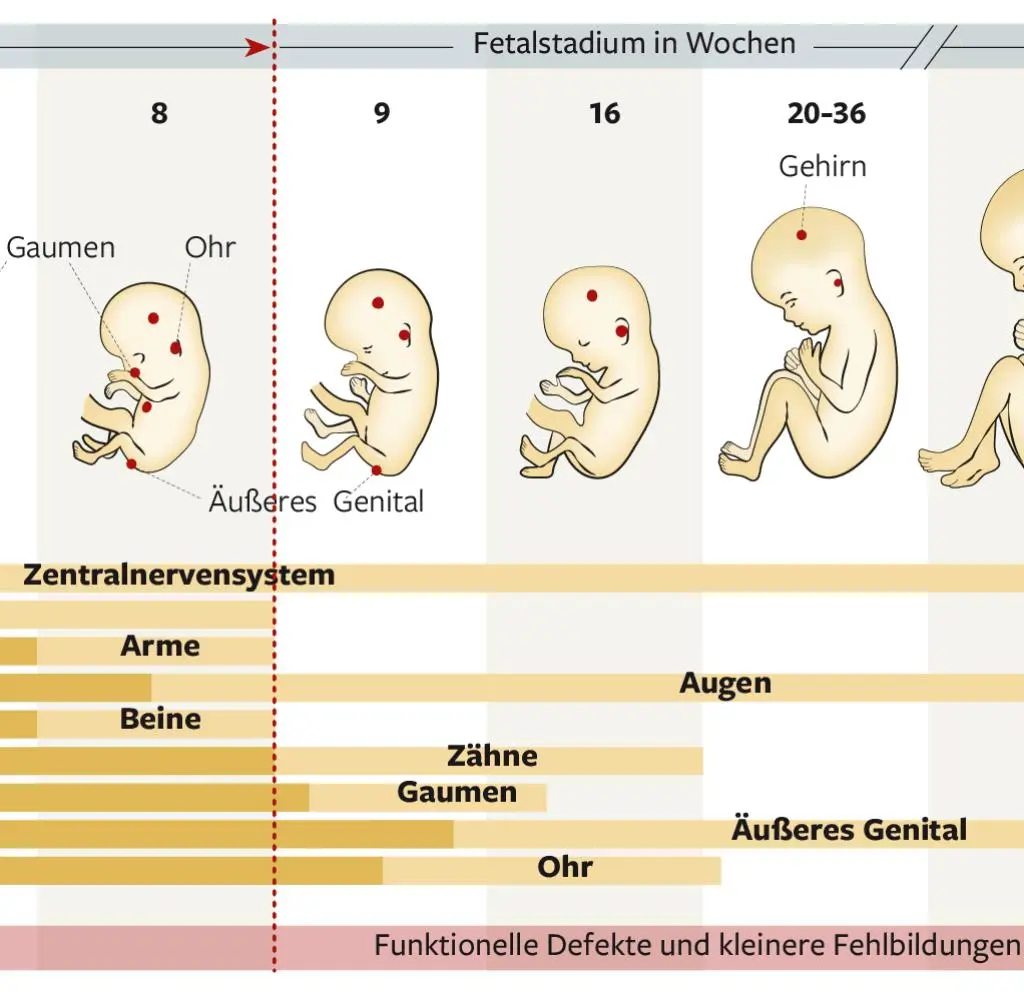

Eine Chromosomenstörung liegt vor, wenn die Anzahl der Chromosomen falsch ist oder wenn ein Chromosom beschädigt ist. Diese Störungen können während der Entwicklung der Eizelle oder des Spermiums oder auch während der ersten Zellteilungen nach der Befruchtung auftreten.

Chromosomenstörungen entstehen zufällig durch Fehler bei der Reifung von Ei- und Samenzellen ( Keimzellen ) oder – seltener – durch Fehler bei der Zellteilung während der Entwicklung der befruchteten Eizelle. Wenn Zellen entstehen, bei denen die Anzahl der Chromosomen nicht mehr stimmt, spricht man von numerischen Chromosomenstörungen bzw. Von Fehlverteilungen der Chromosomen auf die Zellen.

Zum Beispiel kann ein Chromosom fehlen, d.h. Es sind nur 45 Chromosomen in der Zelle, oder es ist ein Chromosom zu viel in den Zellen, d.h. Die Zelle besitzt 47 anstatt 46 Chromosomen.

Auswirkungen von Chromosomenstörungen

Die Auswirkungen einer Chromosomenstörung können sehr unterschiedlich sein. Manche Störungen führen nur zu leichten Auffälligkeiten, während andere schwere körperliche und geistige Behinderungen verursachen können.

Einige Chromosomenstörungen verhindern auch das Entstehen einer Schwangerschaft oder verursachen frühe Fehlgeburten.

- Körperliche Behinderung: Manche Chromosomenstörungen können zu körperlichen Behinderungen führen, z.B. Zu Herzfehlern, Fehlbildungen der Gliedmaßen oder zu Problemen mit den Sinnen.

- Entwicklungsverzögerung: Kinder mit Chromosomenstörungen entwickeln sich oft langsamer als ihre Altersgenossen.